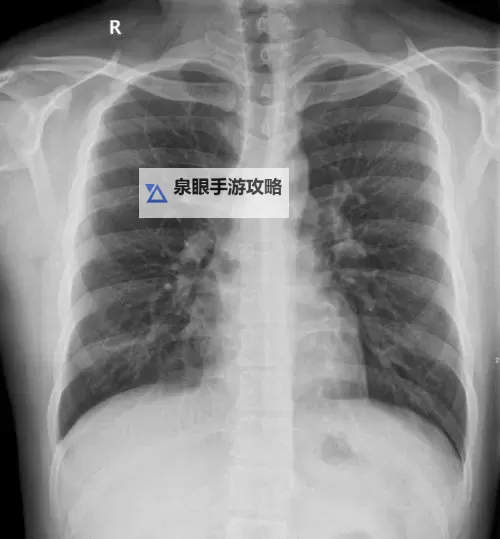

近年来,随着人工智能(AI)和大数据技术的快速崛起,医疗影像的诊断效率与准确性得到了显著提升。AI算法能够辅助医生快速筛查胸片,识别早期肺结节、肺炎、肿瘤等潜在疾病,为提前干预提供重要依据。而免费胸片的推广,则是科技与公共医疗服务深度融合的典范。通过降低经济门槛,让更多患者得以享受高质量的诊断服务,体现了医疗公平与人性化的理念。

未来医疗影像的趋势主要集中在几个方面:一是AI的深度融合;二是影像设备的硬件升级;三是影像数据的互通共享。人工智能不仅帮助提升诊断速度,更通过学习大量病例不断优化算法,逐步实现智能辅助诊断的自动化。同时,高端影像设备的不断研发,使得影像的清晰度和细节呈现更加逼真,辅以虚拟现实(VR)和增强现实(AR)技术,为医生提供更直观的三维立体观察体验。这些技术的集成,大大提升了诊断的准确率和效率。